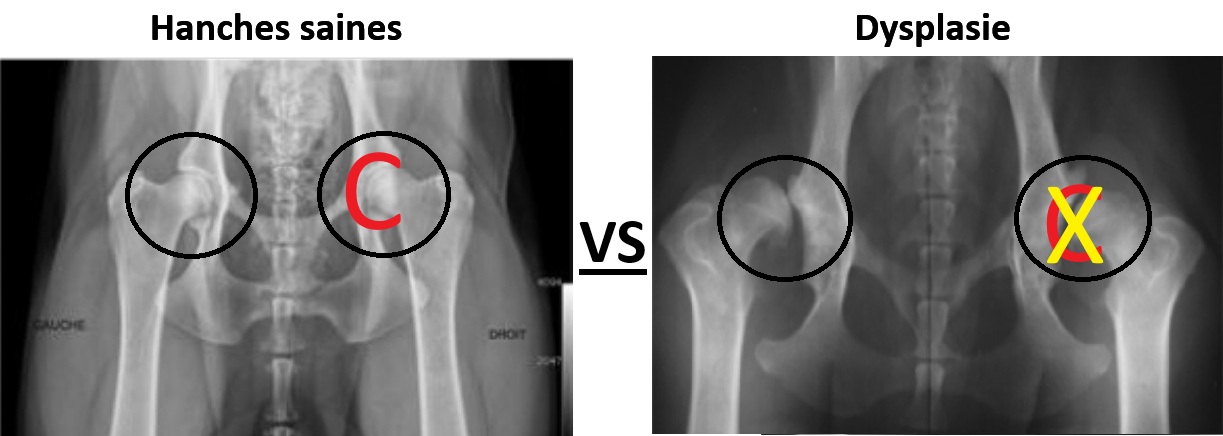

Diagnostic des problèmes de hanche

Le

diagnostic

commence par un examen clinique effectué par un vétérinaire.

Les radiographies sont souvent utilisées pour confirmer la

présence de problèmes de hanche et évaluer leur gravité.